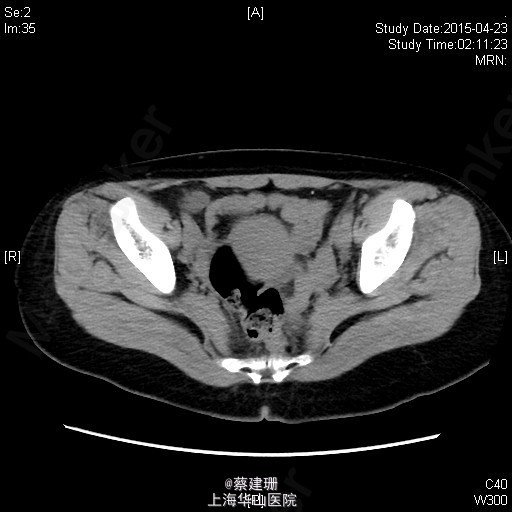

急性阑尾炎(粪石?)伴局限性腹膜炎

患者 女性 24岁,因“转移性右下腹痛一天余。”入院。患者一天前无明显诱因下出现中上腹疼痛,无恶心呕吐,无腹泻。10小时前疼痛转移至右下腹,原先中上腹疼痛缓解,无发热无腹泻。患者未予重视,后疼痛难忍于今日凌晨至我院急诊就诊,血常规示:WBC:18.63*10^9/L,我院B超示:右下腹见肠段局限性扩张,炎性病灶待排。肝胆胰脾肾未见明显异常,双输尿管未见扩张。我院CT示:阑尾增大壁增厚内见高密度影及低密度气体影,符合阑尾炎改变,盆腔少量积液。患者拒绝行急诊手术,故予以保守治疗,患者症状未缓解,右下腹疼痛加重。为行进一步诊治,收入院。

全身皮肤粘膜未见异常,无肝掌,全身浅表淋巴结无肿大。腹平坦,腹壁软,右下腹压痛,伴有肌紧张及反跳痛,麦氏点压痛(+),肝脾肋下未触及,肝肾脏无叩击痛,肠鸣音4次/分。 辅助检查:血常规示:WBC:18.63*10^9/L,N:89%。我院B超示:右下腹见肠段局限性扩张,炎性病灶待排。肝胆胰脾肾未见明显异常,双输尿管未见扩张。我院CT示:阑尾增大壁增厚内见高密度影及低密度气体影,符合阑尾炎改变,盆腔少量积液。

入院后诊断:急性阑尾炎伴局限性腹膜炎。完善相关检查,全麻下行腹腔镜下阑尾切除术。术后恢复可,伤口无明显渗出,予以出院。